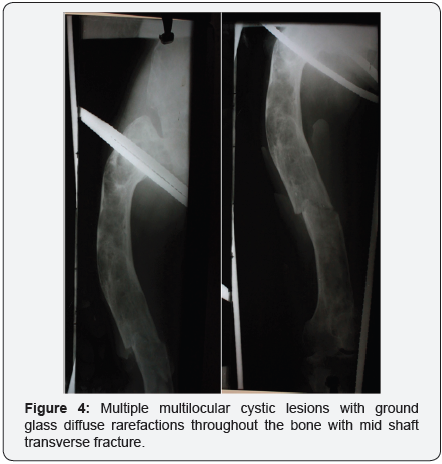

Case study: A 25 year old female presented with fracture in right femur after a trivial trauma. X-ray showed multiple multilocular cystic lesions with ground glass diffuse rarefactions throughout the bone with mid shaft transverse fracture. Similar lesions were seen in B/L Proximal humerus and Rt pelvis. Base of the skull showed Hyperostotic Bone formation. Bone Biopsy showed the mesenchymal stroma surrounding the dysplastic trabeculae is relatively hypocellular. There is a lack of osteoblastic rimming surrounding the dysplastic trabeculae. Both features are characteristic of fibrous dysplasia. The patient was managed with bisphosphonates and Thomas knee splint and union was seen in 2 months.

- Multiple multilocular cystic lesions with ground glass diffuse rarefactions throughout the bone with mid shaft transverse fracture.

- Similar lesions were seen in B/L Proximal humerus and Rt pelvis.

- Overlying cortex was thinned and expanded with thickened medial cortex with a typical ‘Shepard’s Crook Deformity’ due to varus deformity of the neck.